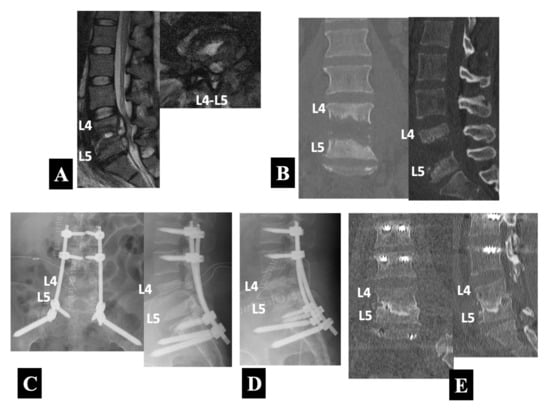

- Case 1 in Group 1-B (Figure 3):